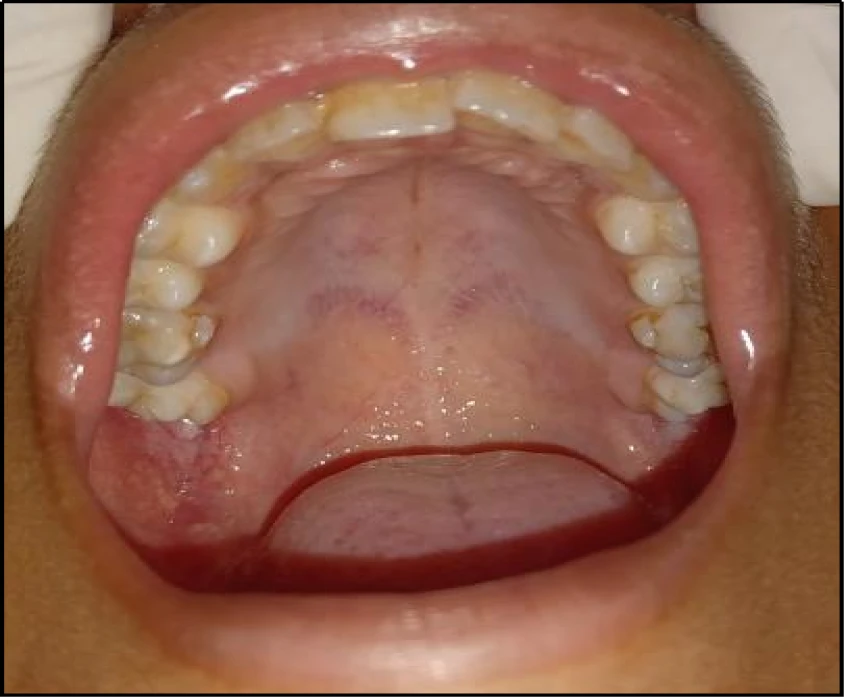

A 14 year old patient reported to the department of Oral Medicine & Radiology with a chief complaint of swelling in his right lower back region of jaw since 4 months. Provisional diagnosis was made as dentigerous cyst i.r.t. 48 based on age of the patient, location of swelling, clinical and radiographic findings. Differential diagnosis was made as Unicystic ameloblastoma (Mural) and Odontogenic keratocyst.

Histopathological report came out to be unicystic ameloblastoma with mural and intraluminal proliferation.